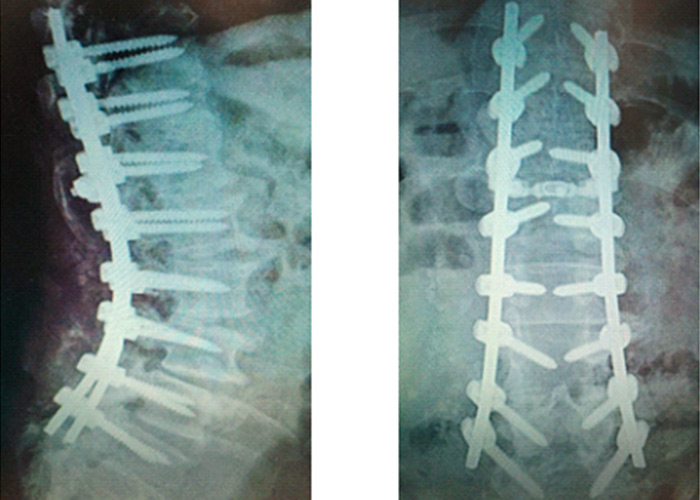

Operación

Diagnosticado de pseudoartrosis, realizamos recambio de tornillos con aumento de grosor y fijación con doble barra con tornillos ilíacos. No es posible realizar artrodesis intersomática L5-S1 por hundimiento de espacio discal intervertebral.

Postoperatorio

Evoluciona muy satisfactoriamente con mejoría importante del dolor y deambulación progresiva con estabilización en la marcha y sin requerir ayuda con bastón ni andador.